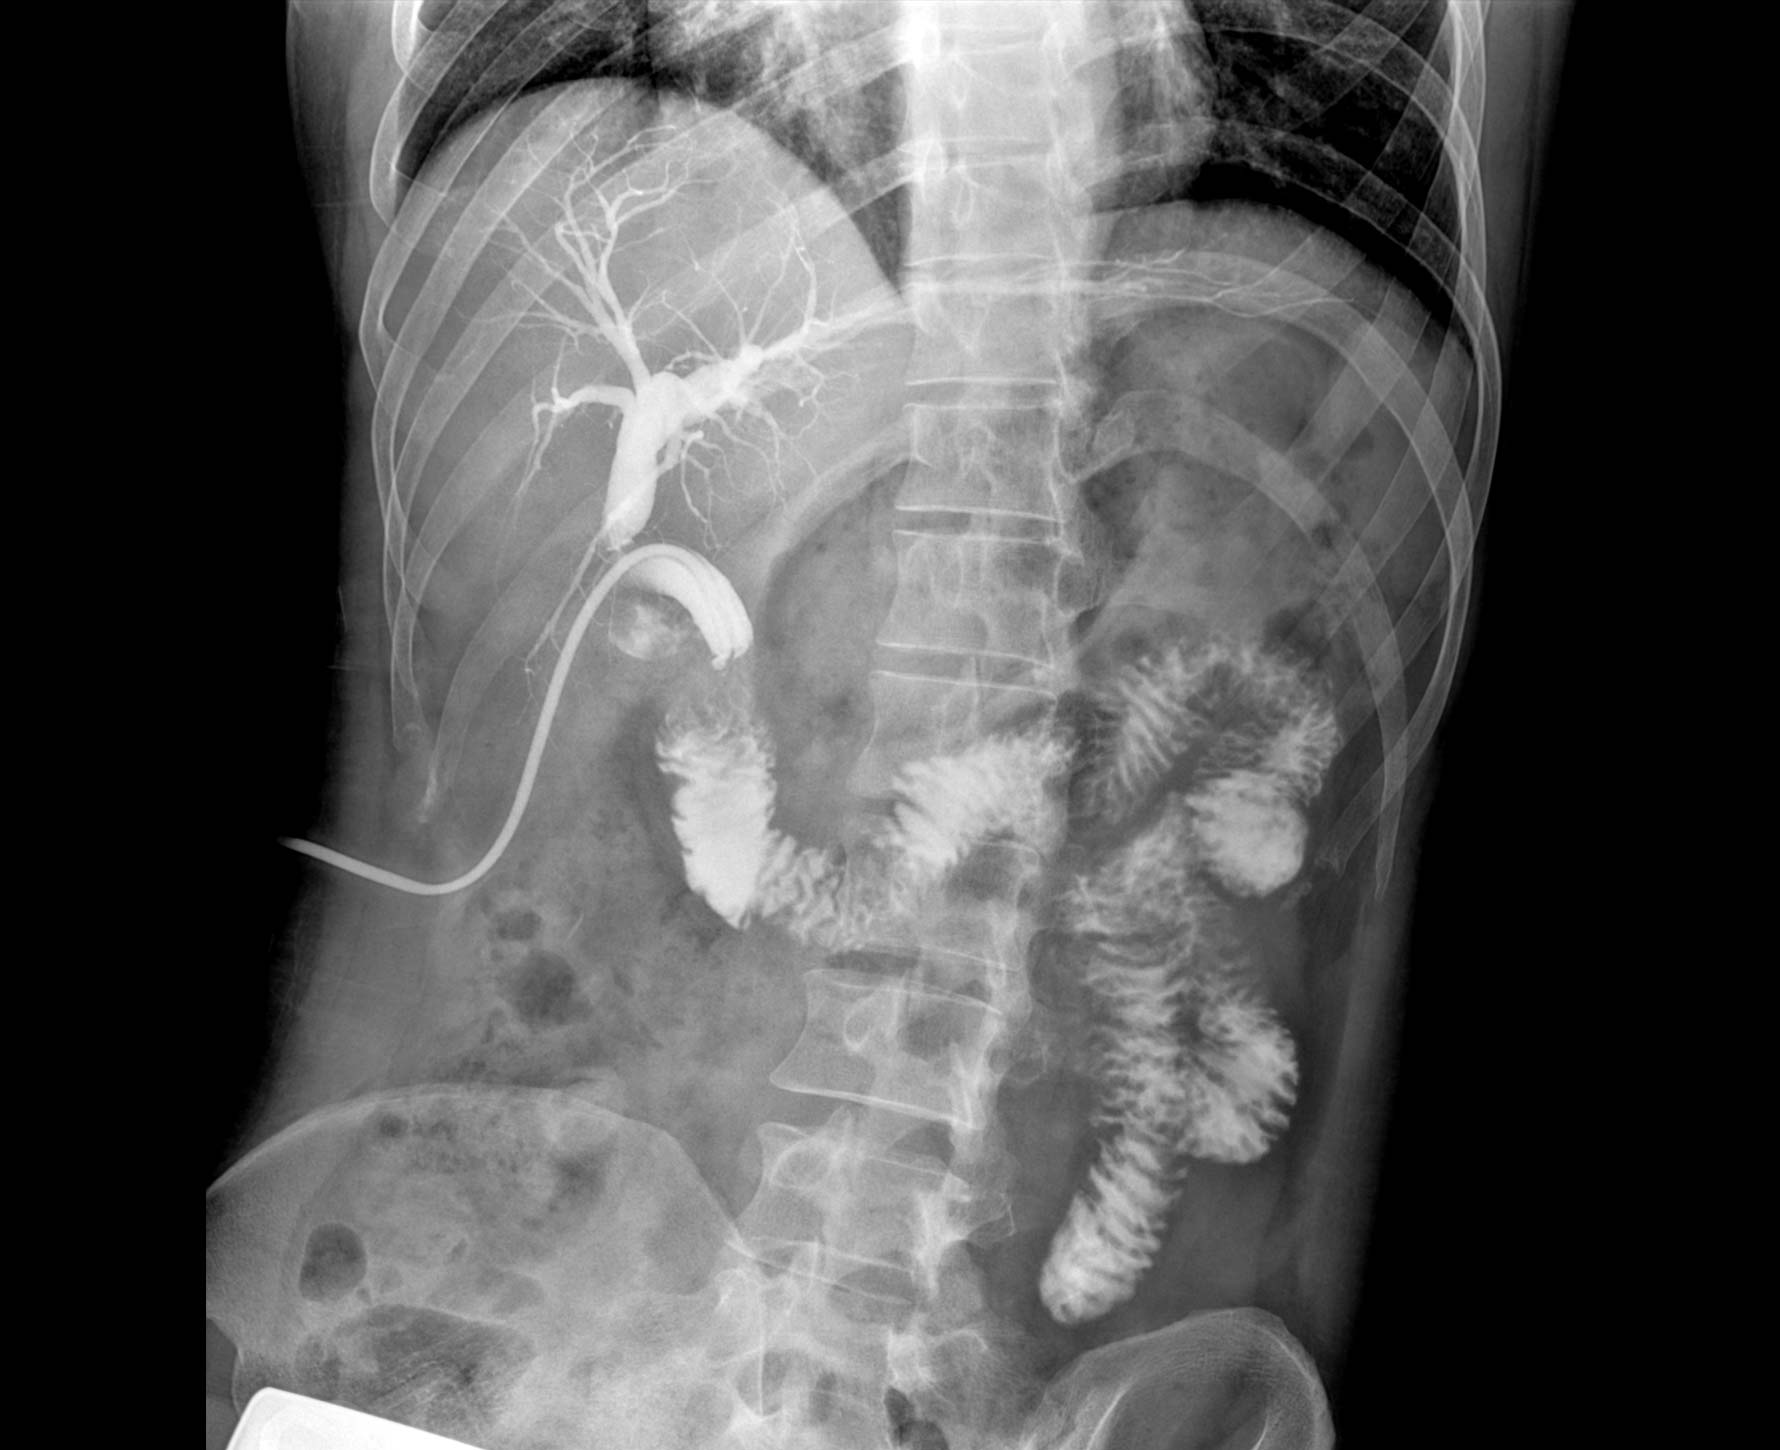

• 造影

适用于各种普通

及特殊胃肠造影检查

• 特有视频保存与回放功能

对胃肠造影检查影像实时保存,多次回放以便确定病灶部位,患者确诊好帮手,减少漏诊。

临床图像